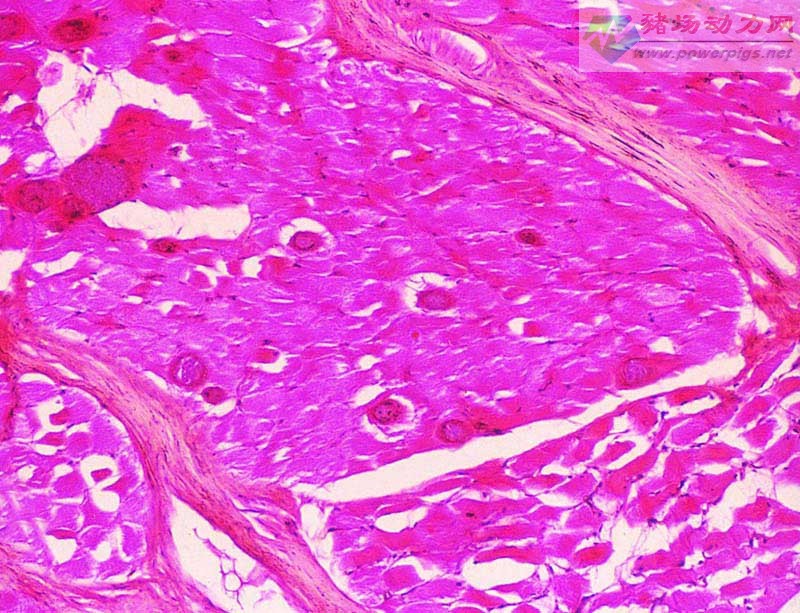

再看几张显微镜下孢子虫的照片发育为滋养体的孢子虫